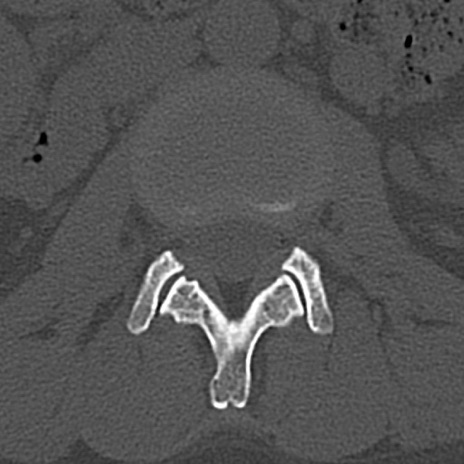

腰椎CT

横断像と矢状断像